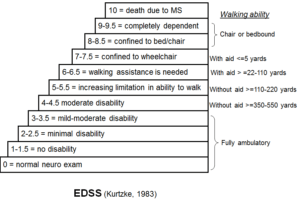

MS is the “D” in MAGIC Dr a helpful mnemonic to remember the primary causes of a rim enhancing brain mass: Metastasis, Abscess, Glioblastoma Multiforme, Infarct, Contusion (trauma), Demyelinating.